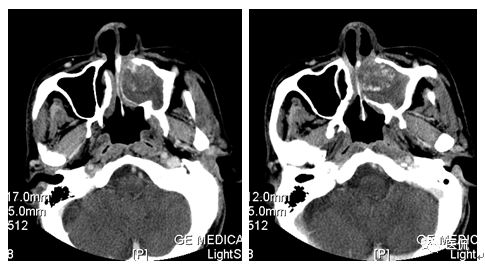

增强水平位FST1WI

CT平扫及增强示:左侧上颌窦及鼻腔可见软组织密度影,呈膨胀性生长,周围骨质压迫性吸收破坏,累及左眶,病灶密度不均匀,周边区可见点状钙化,增动脉期轻度强化,局部见小灶性稍高密度区,静脉期病灶内见不均匀明显强化,CT值最高达117HU,延迟期强化范围有所增大。

本例病灶较大,周围骨质可见吸收破坏,并累及眼眶,病灶内少量钙化,增强扫描具有一定特征性,表现为动脉期轻度强化,局部见小灶性稍高密度区,静脉期病灶局部呈明显强化,CT值最高达117HU,延迟期强化范围有所增大,呈延迟渐进性强化的特点,推测为病灶内出血所致。